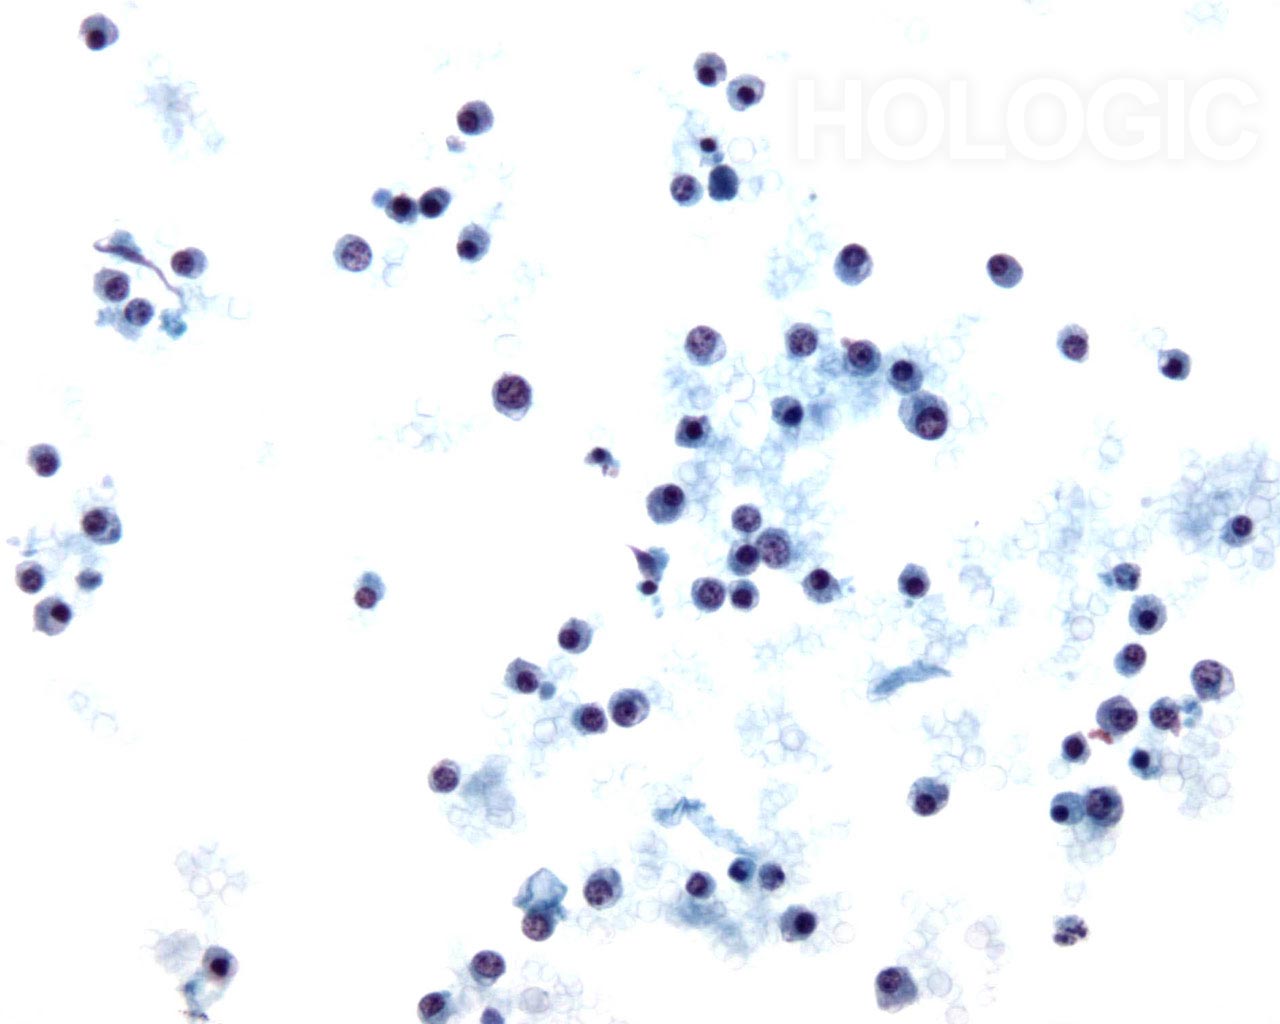

20X

Pleurale effusie:

Non-Hodgkin lymfoom.

60X

Afbeeldingen 35-36:

De neoplastische lymfocyten op deze twee foto’s lijken misschien klein en monotoon, maar ze zijn beduidend groter dan de achtergrondlymfocyten. Kernen zijn vesiculair, met spleten in de kern en lobvorming. De prominentie van de nucleoli varieert.